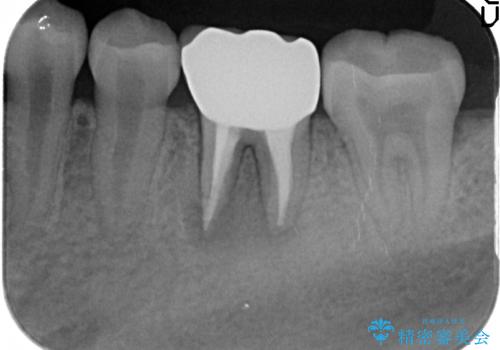

- 咬むと痛む左下6の歯を他院にて診てもらったところ抜歯しかないと言われたが、どうしても残したいと当院にいらっしゃった方の症例です。

検査の結果、根尖病変が大きくポケットも 10mm 以上ありましたが、マイクロ(顕微鏡)にて精査したところ歯根破折は認められなかったため、再根管治療を行いました。

咬合痛等の症状の緩解、根尖病変の縮小傾向、および深かったポケットが正常値まで改善したことを確認後、オールセラミッククラウンによる補綴を行いました。